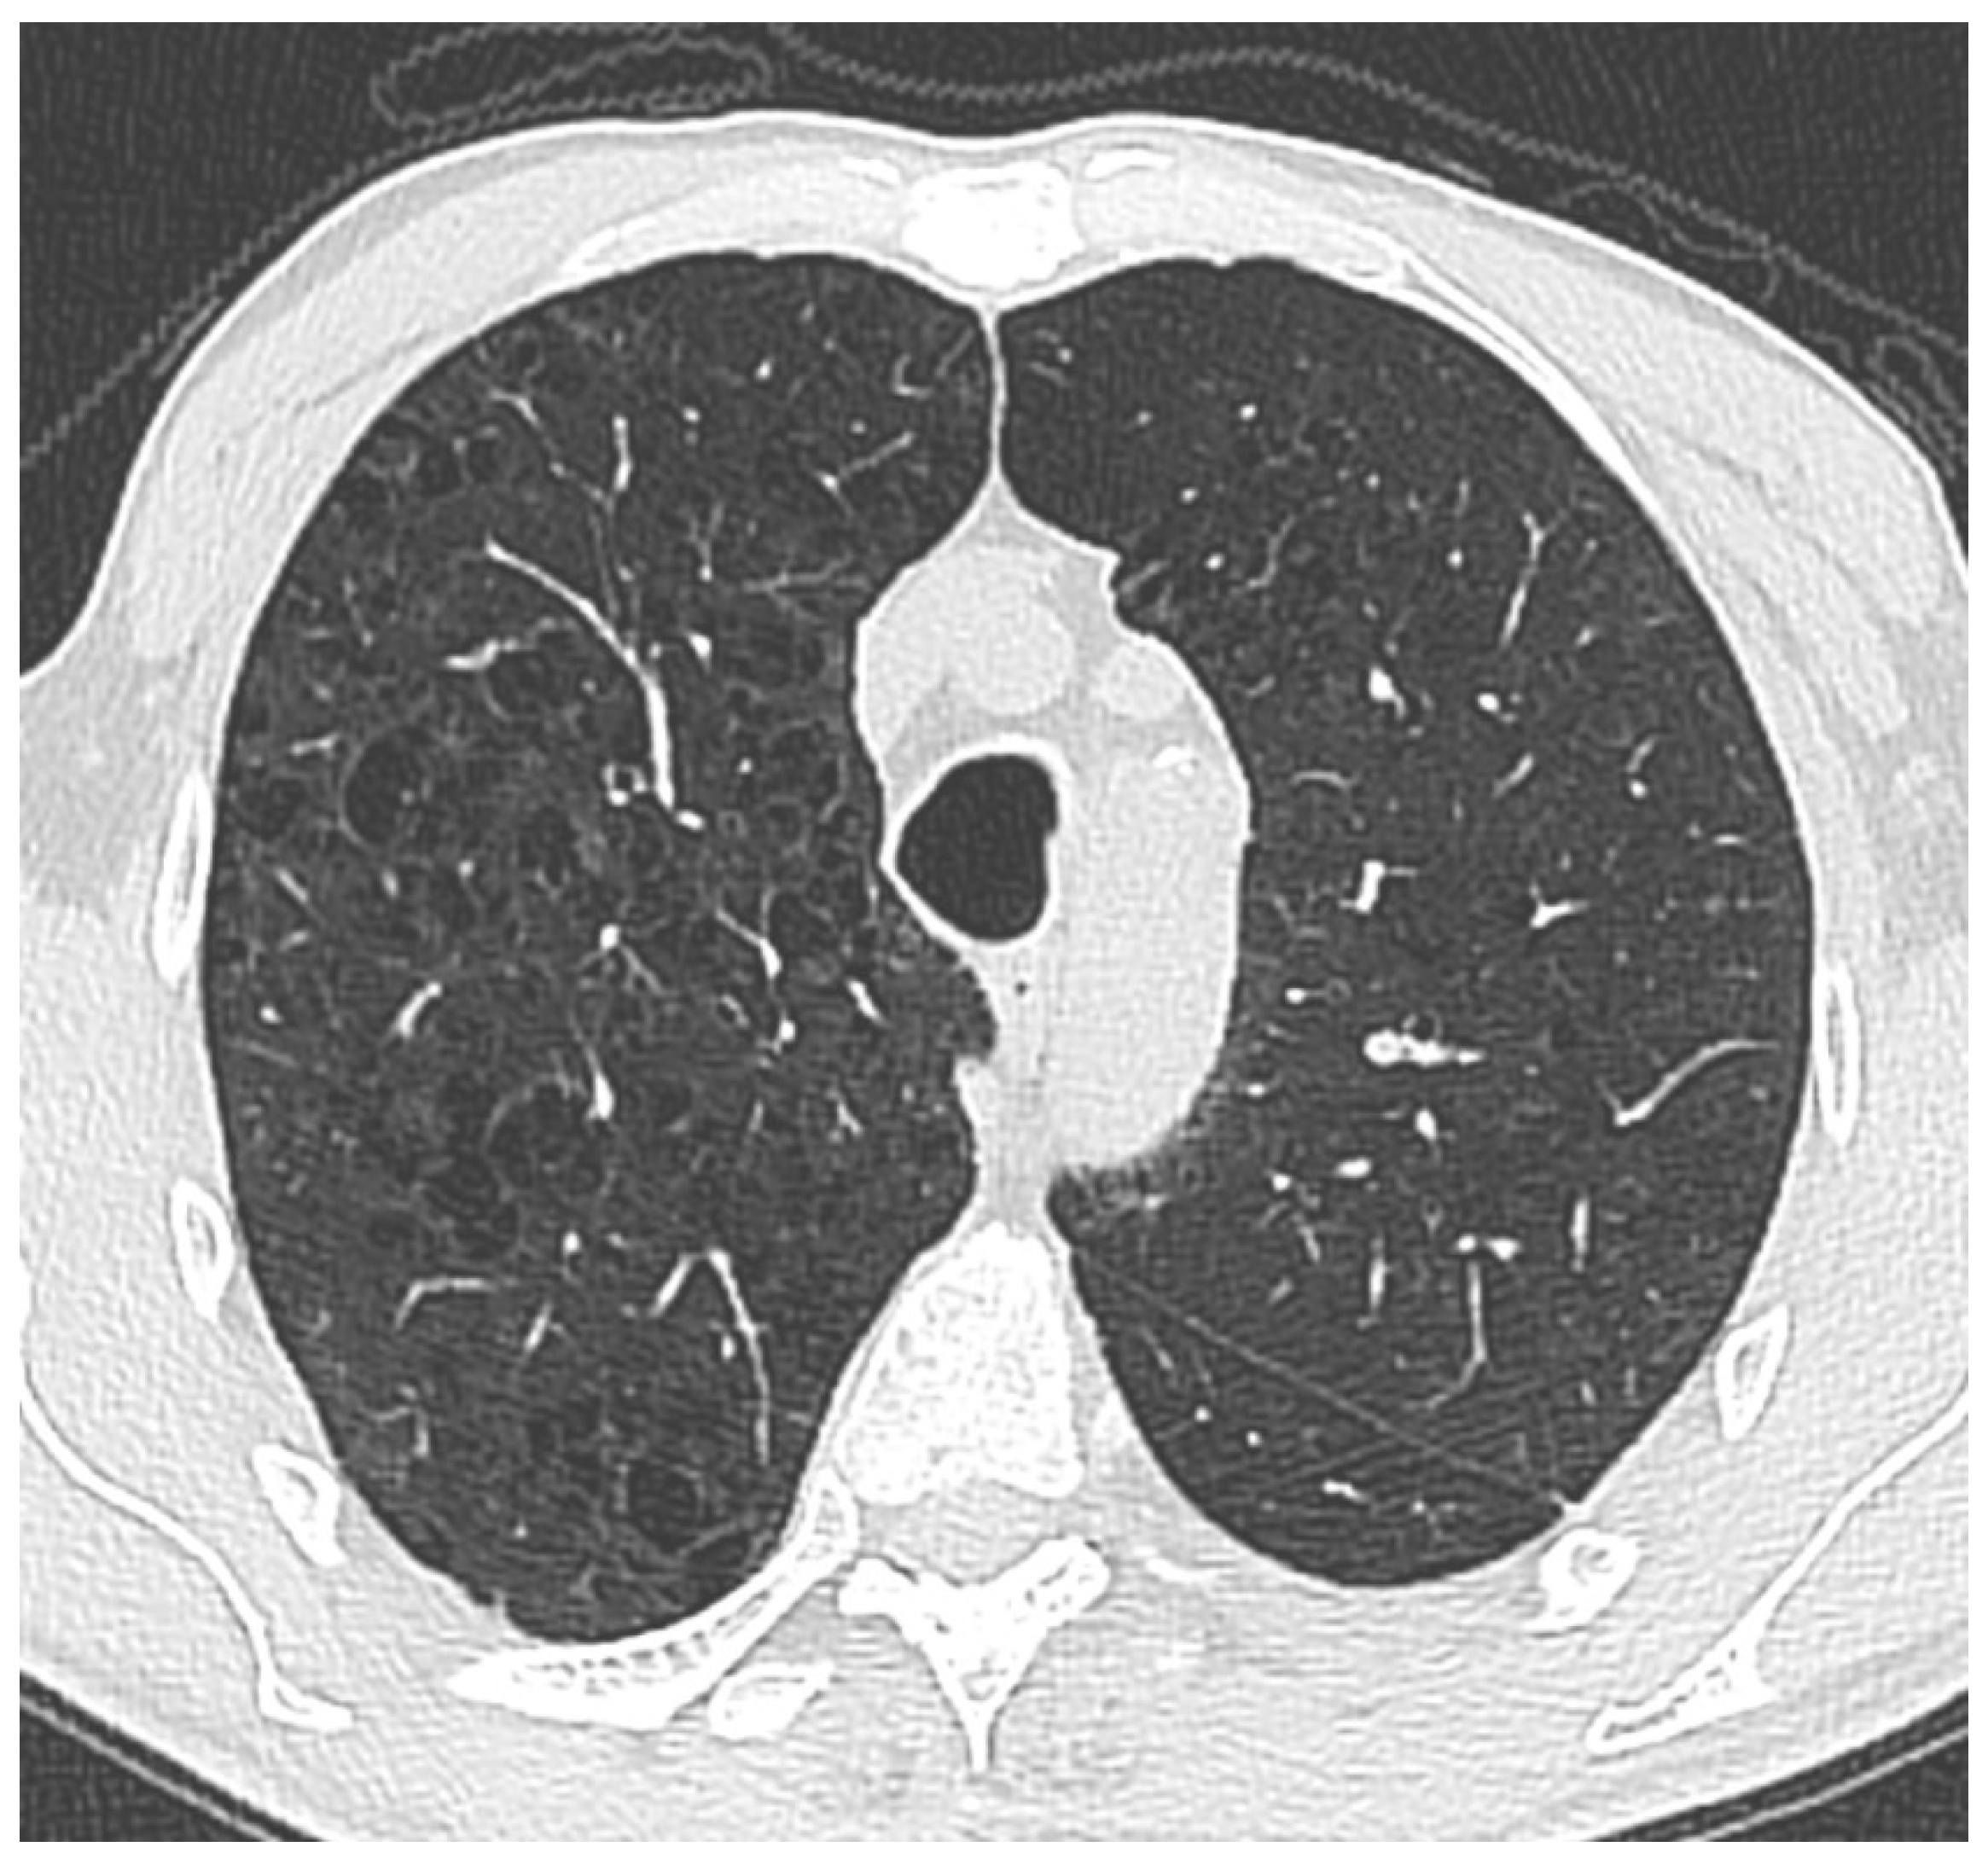

Figure 1. Thoracic CT image demonstrates widespread, small, irregularly shaped areas of low attenuation predominantly located in the upper lobes of both lungs. These findings are suggestive of centrilobular emphysema. The lesions’ absence of peripheral distribution and their proximity to the central bronchioles are consistent with a typical centrilobular pattern.

Preprints 156152 g001